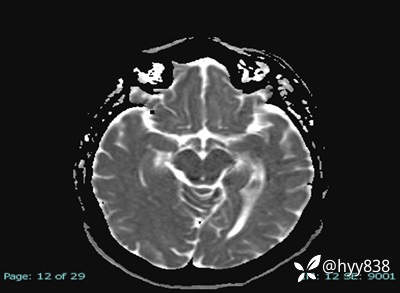

MRI sag T1WI + axi T2WI+FLAIR

DWI